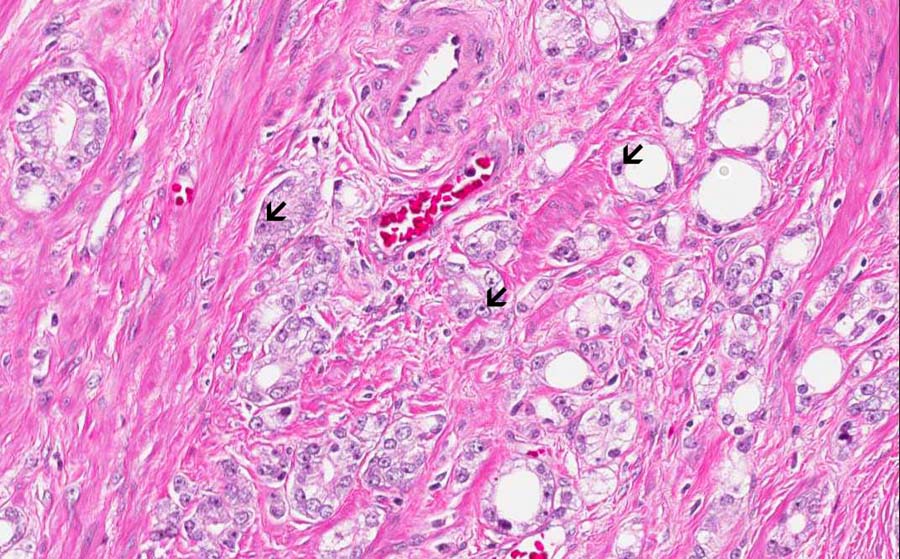

Area 5: This tumor has extracapsular invasion (arrow) into the periprostatic adipose tissue (A).

Hematoxylin & eosin

These are additional high-magnification images to show nuclear details. Note the enlarged nuclei.